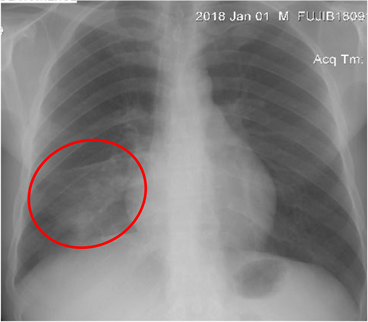

Of the 753 radiographs obtained, 712 were normal (94.55%), while 41 X-rays (5.44%) showed abnormalities (Table 2), thus 14 cases (1.85%) of blunting of left costophrenic angle, 9 cases (1.19%) bunting of right costophrenic angle, 8 cases (1.06%) of cardiomegaly, 3 cases (0.39%) of basal infiltrate, 6 cases (0.79%) of apical infiltrate and one case (0.13%) of right pleural liquid effusion of mean abundance with right para-tracheal opacity. Among these abnormalities 40 cases (5.31%) were considered sequelae and one case (0.13%) as evolutionary (Figure 2).

The figures below show the examples of sequelae (Figures 3-5) and evolutionary (Figure 6) abnormalities encountered.

Figure 4. Right basal infiltrate (red circle).